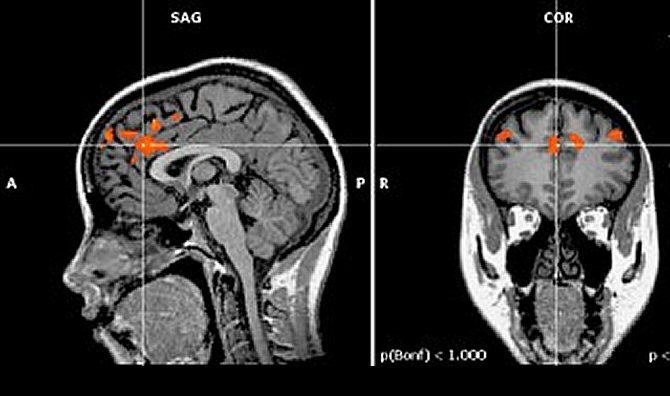

Las imágenes obtenidas en la nueva investigación muestran que la corteza cingulada anterior, la parte del cerebro que reconoce una situación en la que se requiere autocontrol, emite sus señales con igual intensidad en cada momento en que la persona se enfrenta a una situación que requiere autodominio. En cambio, la corteza prefrontal dorsolateral, la parte del cerebro que ejerce el autocontrol, emite sus señales con menos intensidad después de haber tenido que actuar poco antes.![[Img #9718]](upload/img/periodico/img_9718.jpg)

Esa pérdida de actividad en la corteza prefrontal dorsolateral parece denotar pues el agotamiento de la capacidad de autocontrol de la persona. La actividad estable en la corteza cingulada anterior sugiere que, en principio, la mente siempre reconoce la necesidad de mantener el autocontrol, como por ejemplo ante una tentación. El problema viene al intentar poner en práctica esa resistencia a la tentación, sobre todo si la persona ha tenido que vencer otras tentaciones recientemente.